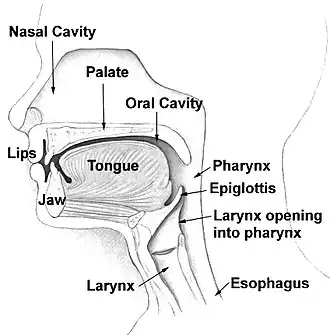

Orthognathic surgery (/ˌɔːrθəɡˈnæθɪk/), also known as corrective jaw surgery or simply jaw surgery, is surgery designed to correct conditions of the jaw and lower face related to structure, growth, airway issues including sleep apnea, TMJ disorders, malocclusion problems primarily arising from skeletal disharmonies, and other orthodontic dental bite problems that cannot be treated easily with braces, as well as the broad range of facial imbalances, disharmonies, asymmetries, and malproportions where correction may be considered to improve facial aesthetics [1] and self-esteem.

It is only recently, and especially with the evolution of oral and maxillofacial surgery in establishing itself as a primary medical specialty – as opposed to its long term status as a dental speciality – that orthognathic surgery has increasingly emerged as a primary treatment for obstructive sleep apnoea, as well as for primary facial proportionality or symmetry correction.

- Skeletofacial discrepancies associated with documented sleep apnea, airway defects, and soft tissue discrepancies

A disproportionately grown upper or lower jaw causes dentofacial deformities. Chewing becomes problematic, and may also cause pain due to straining of the jaw muscle and bone. Deformities range from micrognathia, which is when the mandible does not grow far forward enough (over bite), and when the mandible grows too much, causing an under bite; all of which are uncomfortable. Also, a total maxilla osteotomy is used to treat the "long face syndrome", known as the skeptical open bite, idiopathic long face, hyper divergent face, total maxillary alveolar hyperplasia, and vertical maxillary excess. Prior to surgery, surgeons should take x-rays of the patient's jaw to determine the deformity, and to make a plan of procedures.[11] Mandible osteotomies, or corrective jaw surgeries, benefit individuals who have difficulty chewing, swallowing, TMJ pains, excessive wear of the teeth, open bites, overbites, underbites, or a receding chin. The deformities listed above can be perfected by an osteotomy surgery of either the maxilla or mandible (whichever the deformity calls for), which is performed by an oral surgeon who is specialized in the working with both the upper and lower jaws.[12] Orthognathic surgery is also available as a very successful treatment (90–100%) for obstructive sleep apnea.[13]

Planning for the surgery usually involves input from a multidisciplinary team, including oral and maxillofacial surgeons, orthodontists, and occasionally a speech and language therapist. Although it depends on the reason for surgery, working with a speech and language therapist in advance can help minimize potential relapse. The surgery usually results in a noticeable change in the patient's face; a psychological assessment is occasionally required to assess patient's need for surgery and its predicted effect on the patient. Radiographs and photographs are taken to help in the planning. There is also advanced software that can predict the shape of the patient's face after surgery,[27][28][29][30][31] which is useful for the planning and also explaining the surgery to the patient and the patient's family.[32] Great care needs to be taken during the planning phase to maximize airway patency.